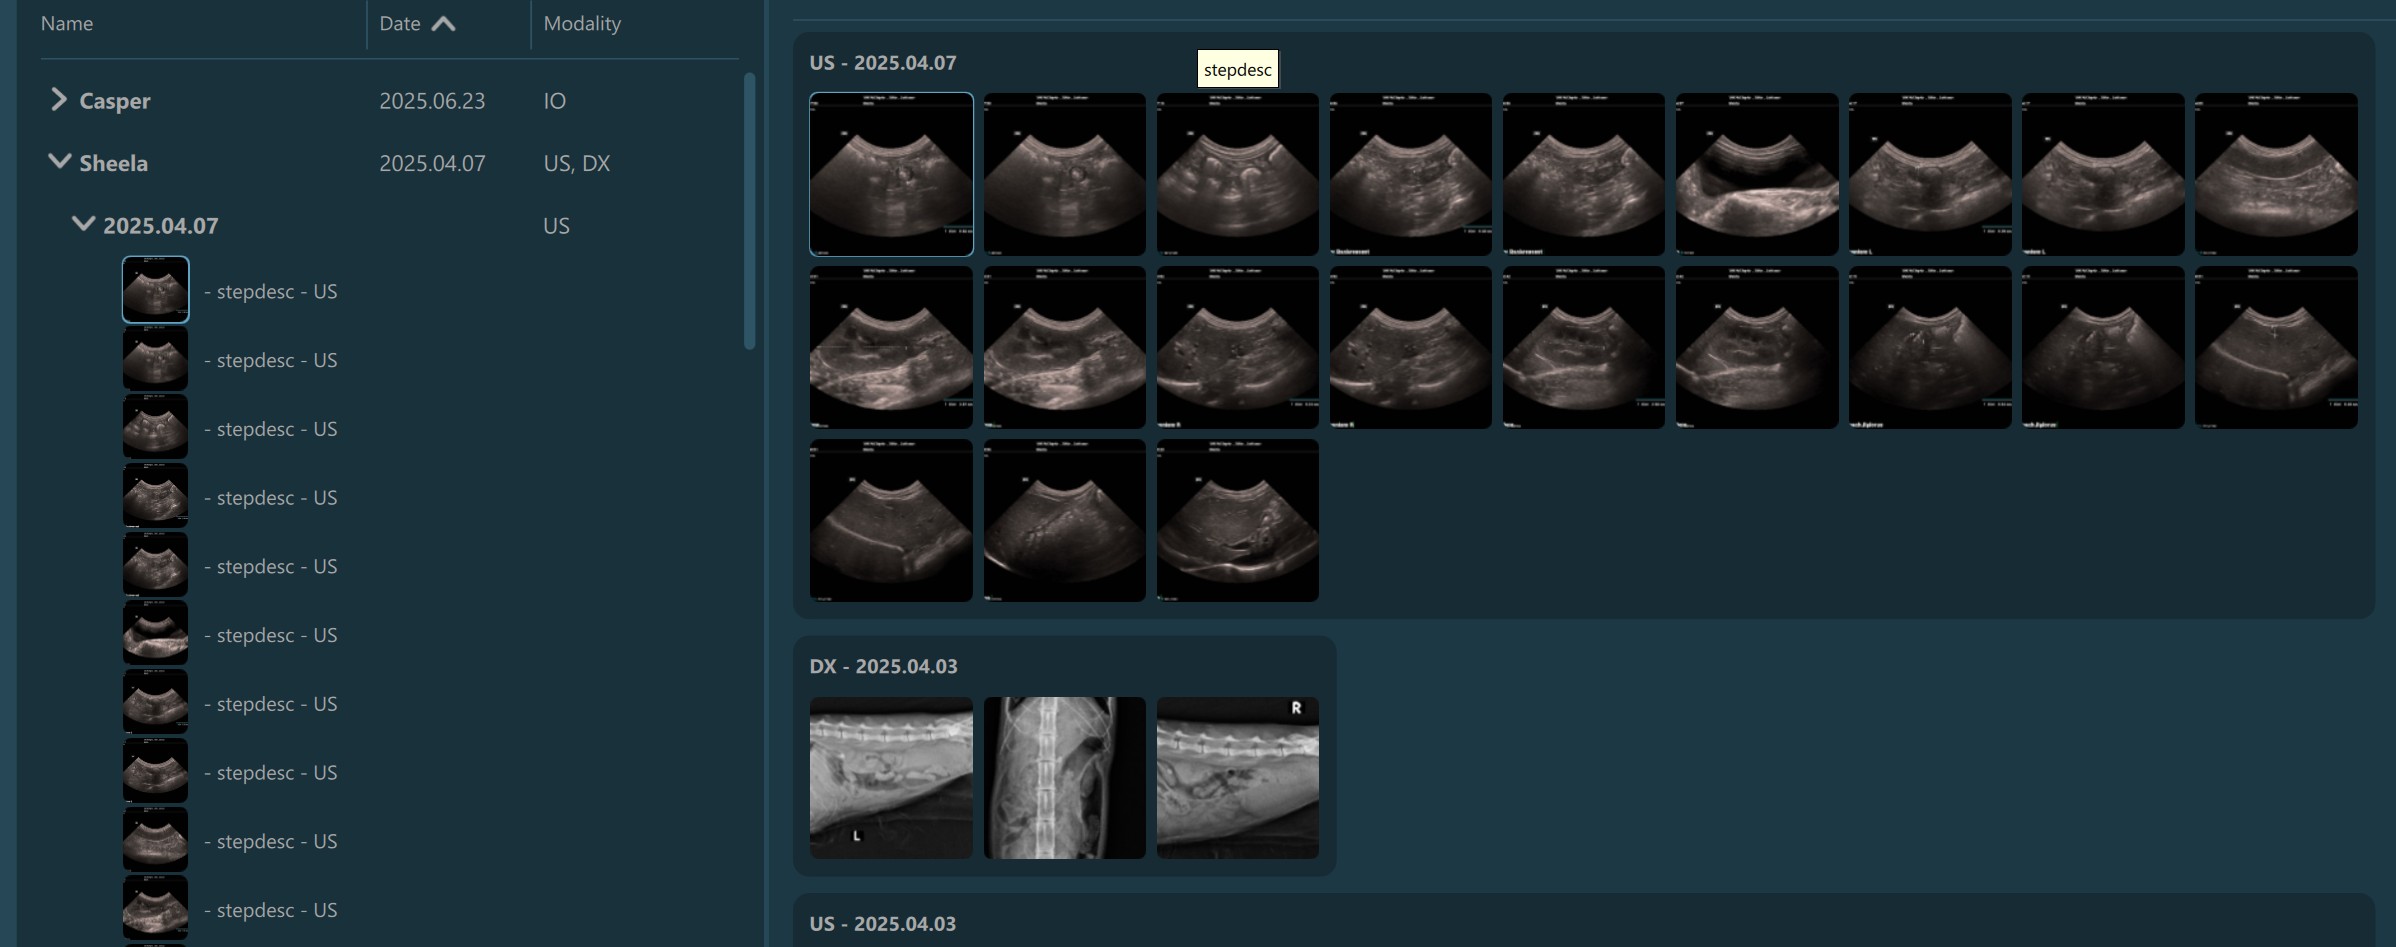

Selecting a patient, study, or series from the Study List opens them and their contents in the Preview Pane, located on the right side of the Study Browser window. In the Preview Pane, the items are separated into sections based on their patient information.

The heading of each section shows the patient name, the latest related study date, patient sex, and owner name. Studies are shown as image groups containing the series as image previews. Each study is highlighted by its modality and date. To view the series description of each series, hover over the desired image preview.

The top right corner of the Preview Pane offers the users the ability to switch the thumbnail preview between unified or keeping the original aspect ratio of the image.

Similar to the selection in the Study List, users have the ability to select patients, studies, or individual series. A highlighted selection in the Preview Pane indicates the active selection in the Study List.

The Preview Pane can also be used to extend or narrow down the selection from the Study List. To select/deselect items in the Preview Pane simply press on them with the mouse.

Additionally, when images are being transferred, a Transferring… label is shown in the heading of the Preview Pane. Moreover, each series in the Preview Pane has its own state indicating whether the transfer is ongoing or it has finished. When all of the selected images have been transferred, the label in the heading of the Preview Pane is changed to Transferred as well.

Transfer of images is in progress:

Transfer of images has been completed: